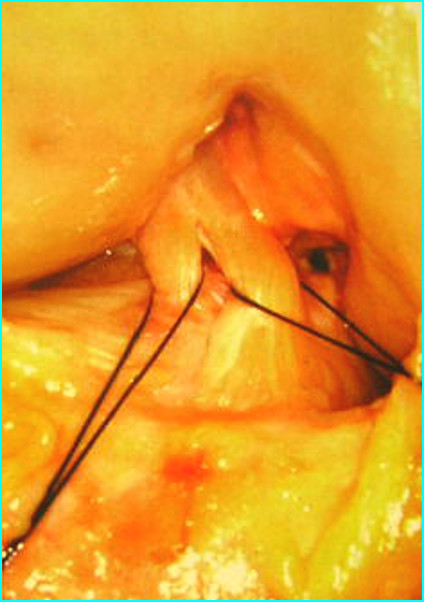

(十四)引入移植腱

利用刚才的爱惜帮牵引线将编织好的移植腱牵拉入隧道内。一般需要1分钟。

(十五)股骨端固定

关节镜确认后移植腱已经按照要求牵拉入隧道后,股骨端自横穿钉套管击入2枚横穿钉固定,拔除套管。此过程一般需要1~2分钟。